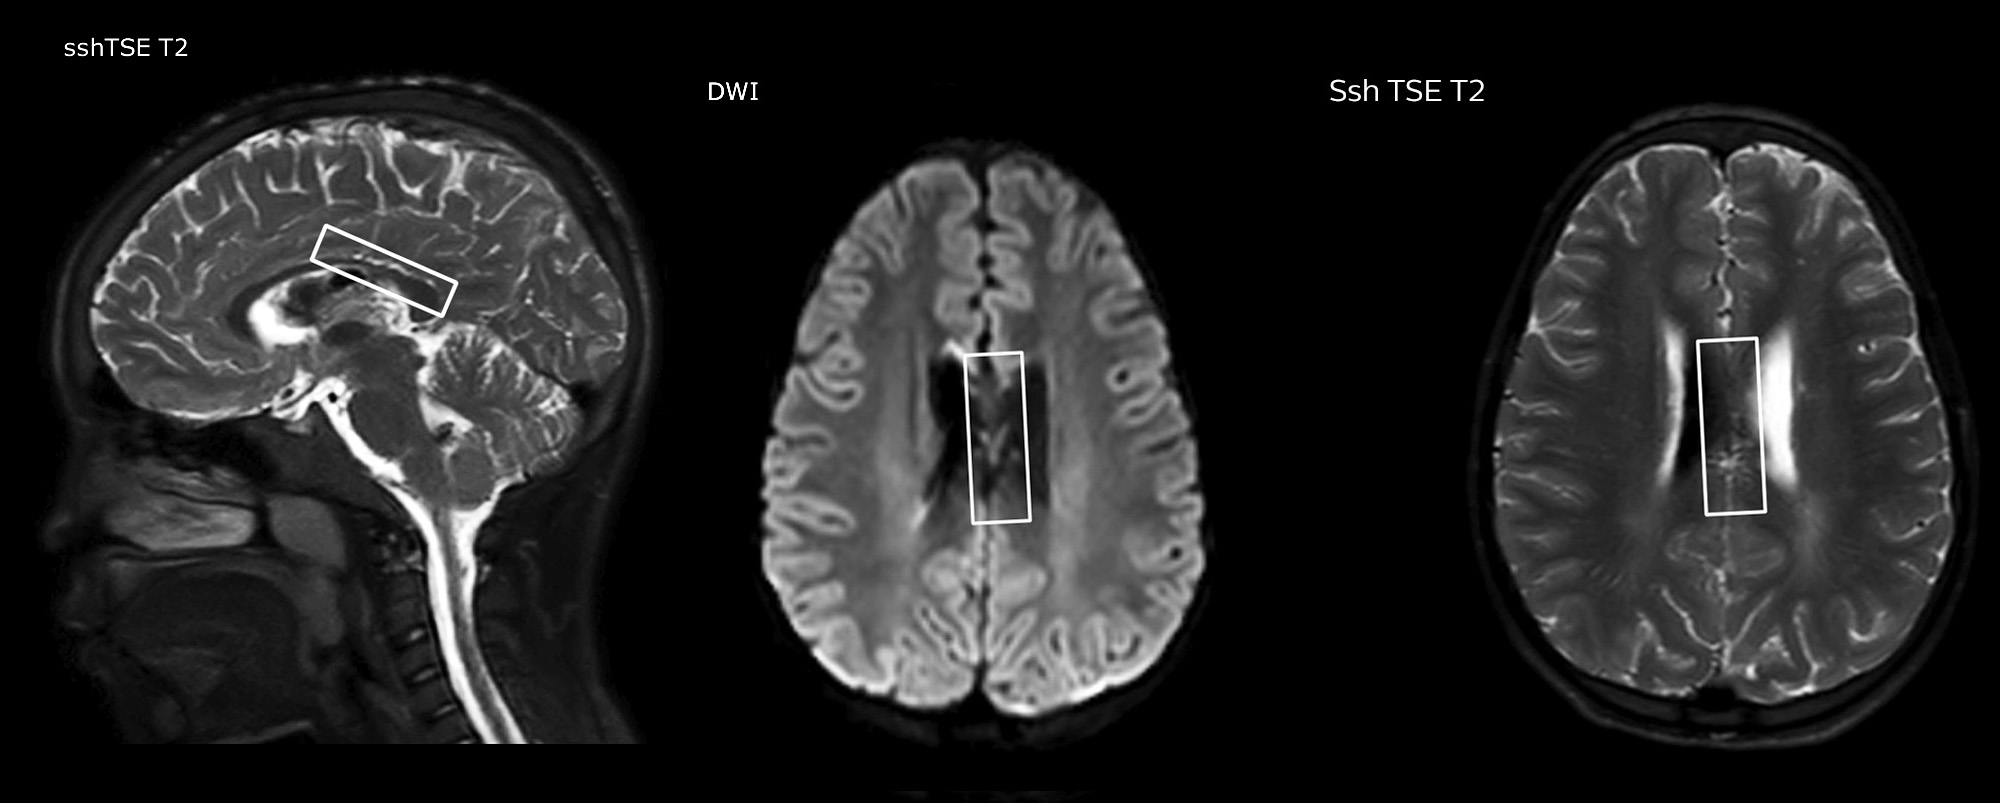

Dr. Miller uses pCASL for all patients who present with chronic and acute cerebrovascular abnormalities such as acute stroke, as well as patients who present with signs of acute inflammation in the brain, and occasionally in patients with tumors, to assess the perfusion status of their tumor.

“In combination with diffusion weighted imaging, it can help give a more extended assessment of the degree of perfusion abnormality in a patient who is suffering acute ischemia. We have a number of patients who have chronic arterial insufficiency due to prior arterial abnormalities or acquired arterial abnormalities such as sickle cell disease or neurofibromatosis. Sometimes the child’s first manifestation of disease progression is a reduction in brain perfusion before stroke symptoms manifest clinically or in diffusion weighted imaging. We use pCASL to help delineate the perfusion abnormality.”

To other new users I would recommend to also start to interpret the pCASL images in comparison with other standard imaging – T2 and FLAIR and DWI – until the user gains confidence in interpreting these images by themselves.”